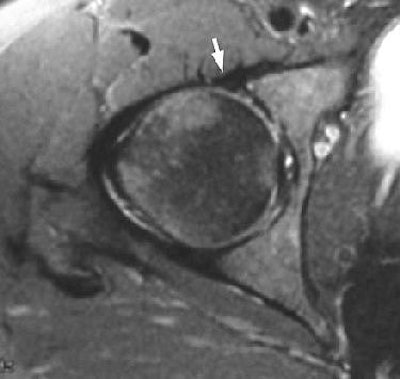

| Axial fat-suppressed fast spin-echo T2-weighted image without intra-articular contrast material (TR/effective TE, 4,000/75; field-of-view, 20 cm) in a 38-year-old woman with hip pain and "locking." Anterior labrum appears diffusely low in signal intensity (arrow) and was therefore interpreted as normal. However, at arthroscopy, patient was found to have anterior labral tear. Toomayan GA, Russell Holman WR, Major NM, Kozlowicz SM, Vail TP, "Sensitivity of MR Arthrography in the Evaluation of Acetabular Labral Tears" (AJR 2006; 186:449-453). |

According to the results, acetabular labral tears were found in 40 of 51 hips at arthroscopy. MR arthrography with a small FOV, and intra-articular contrast, found 24 acetabular labral tears in 30 hips for a sensitivity of 92%. Unenhanced conventional MRI with a large FOV revealed 12 tears in 21 hips for a lackluster sensitivity of 8%. Conventional, no-contrast MRI with a small FOV turned in a sensitivity of 25%.

MR arthrography with a small FOV "allows excellent assessment of the acetabular capsular-labral complex," the group concluded. In addition, "contrast material in the joint can make the distinction more apparent because the contrast material and cartilage are of different signal intensities."